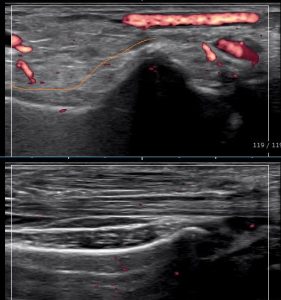

掌側(手のひら側)からみるとこんな感じです。

上下の違いわかりますか??

上の画像が折れている手・下の画像が折れてい方

オレンジの線が曲がっているのわかりますか?

背側からみて、これなら大丈夫だ。

折れてないと思ったら・・・・

折れてました(泣)

顧問医の先生にレントゲン検査をお願いし、

橈骨下端部骨折の診断を頂きました。